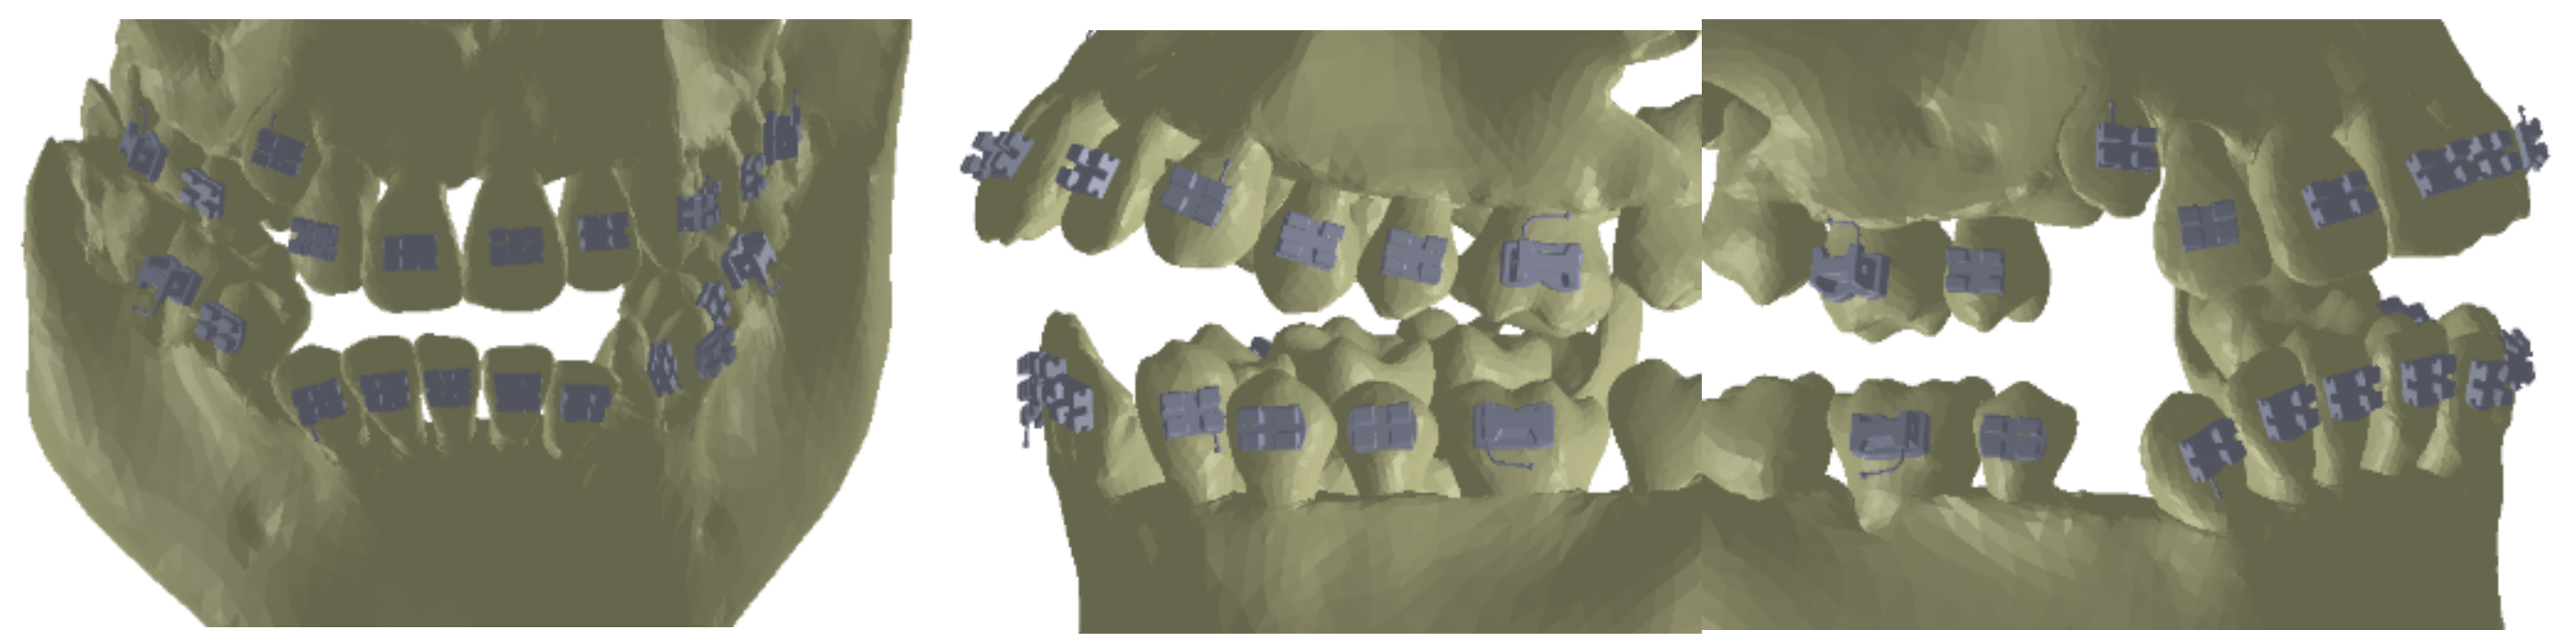

As the first step, we placed the bracket and tube elements on the vestibular surfaces of the teeth using CAD methods and techniques in the Assembly module of SolidWorks, as shown in Figure 16.

Figure 16. Location of the bracket and tube elements.